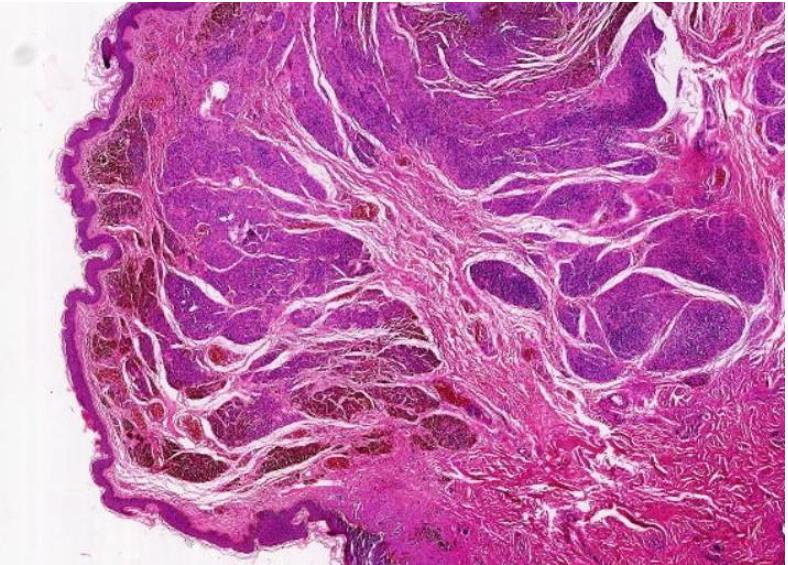

病变组织制成厚约数微米的切片,通常用苏木精·伊红染色(HE染色),或其他方法染色后,用光学显微镜观察其微细病变。

到目前为止,传统的HE染色组织学观察方法仍然是病理学诊断和研究最基本的方法,还没有其他方法能够取代。

▲所以组织病理切片的制作流程,耗时较长,为了诊断准确,真的快不了